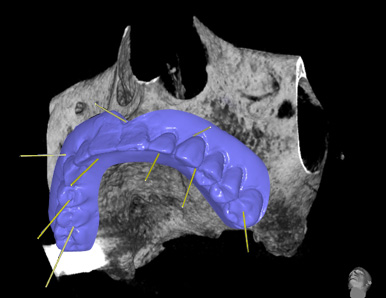

Su richiesta del paziente, si decide di eseguire una protesi fissa su impianti con chirurgia computer-guidata. Dopo Tac arcata superiore e scansione 3D del progetto protesico, si esegue l'accoppiamento virtuale di entrambi. Su questo si progettano profondità e inclinazione degli impianti che vengono inseriti virtualmente. Si realizza poi una dima chirurgica e una protesi. Quindi in maniera assolutamente non invasiva vengono inseriti flapless 6 impianti e successivamente, dopo adattamento, avvitata la protesi toronto. (intervento e foto eseguiti da me in 2h e 30 min)